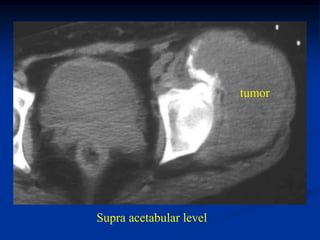

Case #1135.1

21 year female with large pelvic mass which turned out to be

a metastatic thyroid metastasis from an ovarian teratoma

Pelvic metastasis seen on PO x-ray following teratoma surgery

tumor

Bone scan

Sciatic notch level

Supra acetabular level